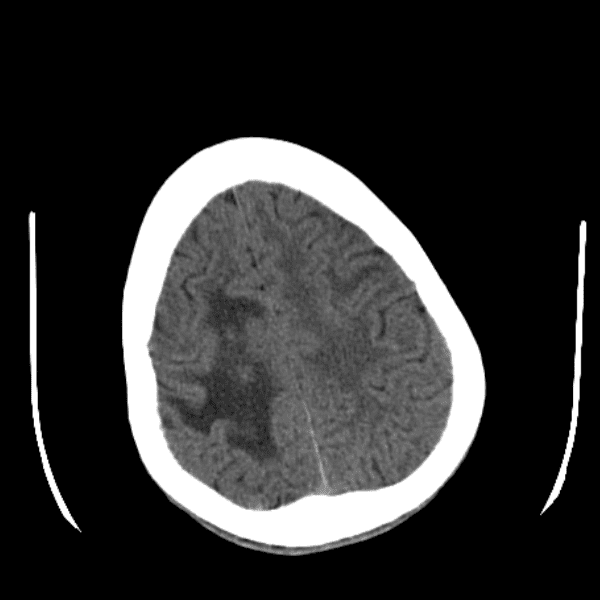

Classic Cases